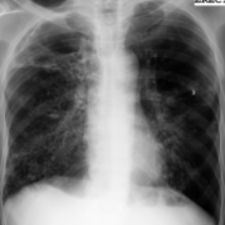

Tuberculosis remains a critical global health issue, particularly in resource-limited and remote areas. Early detection is vital for treatment, yet the lack of skilled radiologists underscores the need for artificial intelligence (AI)-driven screening tools. Developing reliable AI models is challenging due to the necessity for large, high-quality datasets, which are costly to obtain. To tackle this, we propose a teacher--student framework which enhances both disease and symptom detection on chest X-rays by integrating two supervised heads and a self-supervised head. Our model achieves an accuracy of 98.85% for distinguishing between COVID-19, tuberculosis, and normal cases, and a macro-F1 score of 90.09% for multilabel symptom detection, significantly outperforming baselines. The explainability assessments also show the model bases its predictions on relevant anatomical features, demonstrating promise for deployment in clinical screening and triage settings.